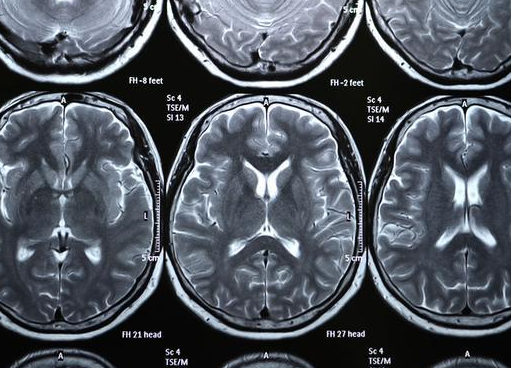

核磁共振摇一摇再看

核磁共振(MR)利用强磁场,使体内的水分振动,然后平静下来,感受里面的振动。

形成成像后,可以观察到正常组织与患病部位的差异。

因此,核磁共振也被戏称为“摇摇晃晃的检查”。

MRI可以从任何角度切割,而且没有辐射。

颅脑、脊柱和脊髓的解剖学和病变表现优于CT;MRI比CT更敏感,尤其是关节、肌肉、中枢神经系统和其他软组织。

MRI对脊柱、关节、肿瘤、传染病、淋巴结和血管结构的相互识别具有独特的优势。

然而,在某些方面,MRI不如CT好。

例如:肺、骨结构的细节、骨折等,所以有时骨科医生会要求两者都要检查;

需要注意的是,体内有金属物体和心脏起搏器的人不应接受核磁共振,检查前应通知医生。